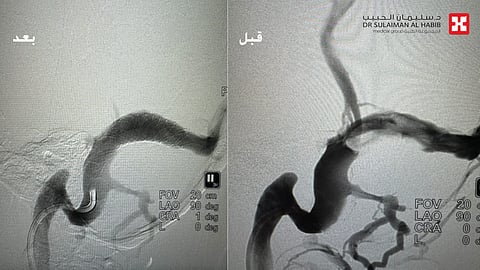

وقال الدكتور الجهني أن النتائج كشفت عن وجود تضيقات شديدة في أوردة الدماغ ، صاحبها حدوث ارتجاع لتدفقات الدم في أورده القشرة الدماغية، وهو الأمر الذي فسر شعور المريضة بطنين الأذن المستمر والنابض، وقرر الفريق الطبي التدخل العلاجي عن طريق عملية قسطرة بدون شق جراحي، وذلك للحيلولة دون إصابتها بالمضاعفات المحتملة والتي من أبرزها الجلطات الدماغية وارتفاع ضغط السائل النخاعي للمخ لا سمح الله.

وأشار إلى أن العملية استغرقت 60 دقيقة فقط، وتم فيها عمل فتحة بطول 2 ملم، وتركيب دعامة خاصة في الوريد الدماغي، إذ إعتدل بعدها ضخ الدم وقل الإرتجاع في أوردة قاع الجمجمة. نقلت بعدها المريضة إلى العناية المركزة لمدة يوم واحد، وبالمتابعه السريريه اتضح وجود تحسن ملحوظ في حالتها الصحية، حولت بعدها إلى جناح التنويم ، مؤكداً أن أعراض الطنين اختفت بصورة شبه كاملة ولله الحمد، وأصبح باستطاعتها سماع الآخرين بشكل واضح، وقد خرجت إلى منزلها في اليوم الثالث وهي بصحة جيدة.